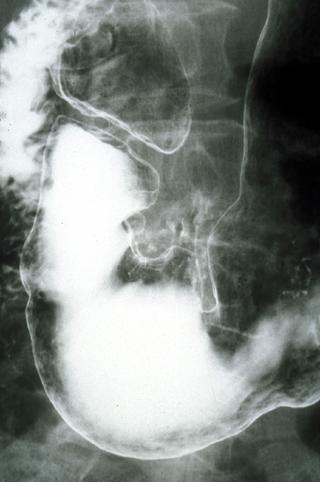

疾患(病理主体)の分類悪性上皮性腫瘍/腺癌

部位(臓器別)胃(部位)/前庭

検査方法X-P

腫瘍の肉眼分類0型(表在型)/IIa型(IIa+IIc)

病変の最大径(ミリ)20〜24

腫瘍の深達度sm